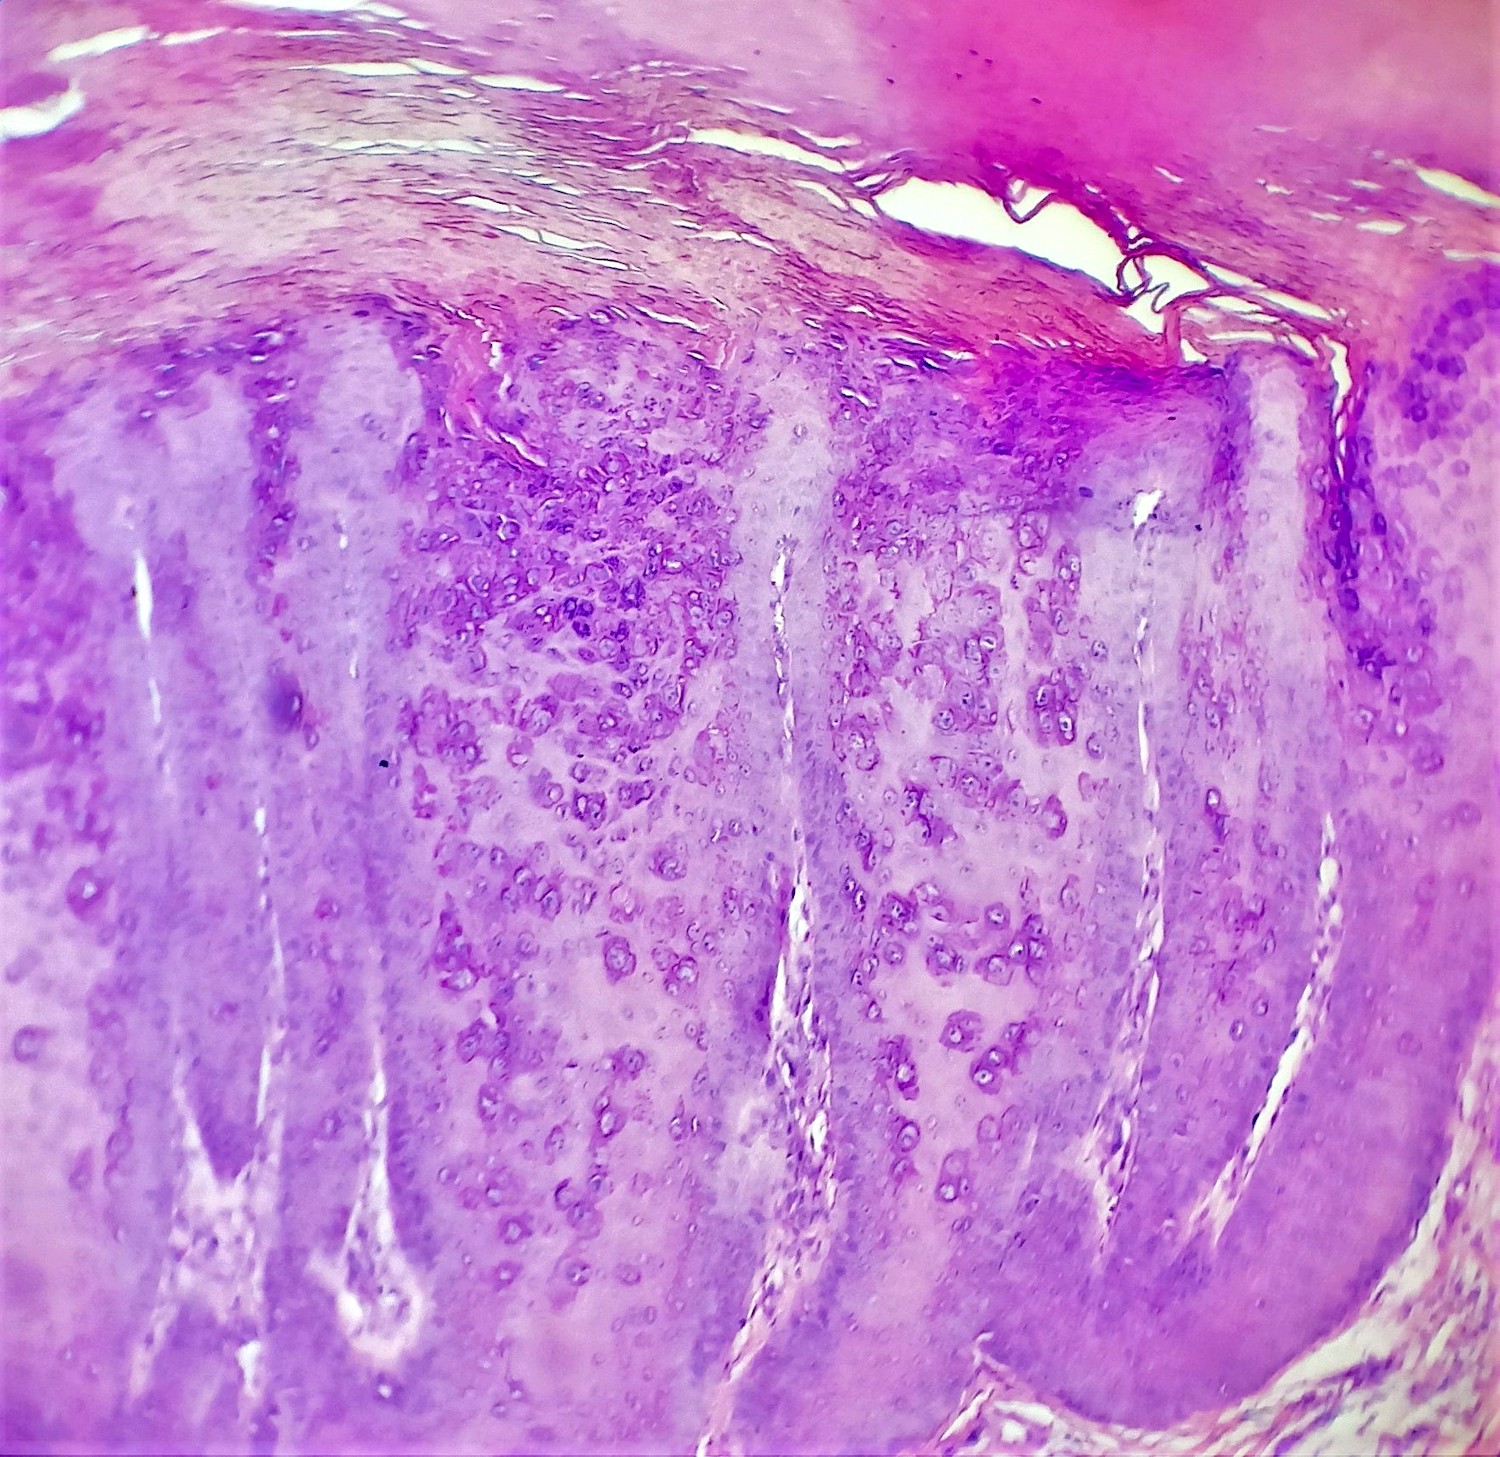

Microscopic (histologic) description

- Common warts (verruca vulgaris) (Arch Pathol Lab Med 2018;142:700):

- Hyperkeratosis, papillomatosis, hypergranulosis

- Columns of parakeratosis, especially over projecting dermal papillae

- Intracorneal hemorrhage

- Inward bending of rete ridges at borders of lesion (toeing in)

- Dilated capillaries in dermal papillae

- Projects above the plane of the epidermis

- Palmar / plantar warts (verruca palmaris and verruca plantaris) (Arch Pathol Lab Med 2018;142:700):

- Similar to verruca vulgaris (clinical distinction based on location)

- Endophytic growth - greater proportion of the lesion lies beneath the plane of the epidermis

- Condyloma acuminatum (venereal / genital warts) (Head Neck Pathol 2019;13:80):

- More massive acanthosis with bulbous rete ridges (condyloma means fist or knuckle)

- Koilocytes in the upper spinous layer

- Parakeratosis ofen in the valleys of the epithelium (crypt parakeratosis) (see condyloma)

Microscopic (histologic) images

Contributed by Heba Ahmed Abdelkader, M.D., Hillary Rose Elwood, M.D., AFIP,

@MirunaPopescu13 on Twitter and @shilpa_rakesh_path on Instagram